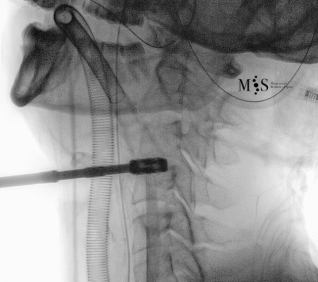

Imágenes de una cirugía de fusión cervical endoscópica

Animación de la inserción de una caja intersomática por vía endoscópica percutánea.

Nótese la apertura (expansión) de la pared posterior del disco al insertar la caja.